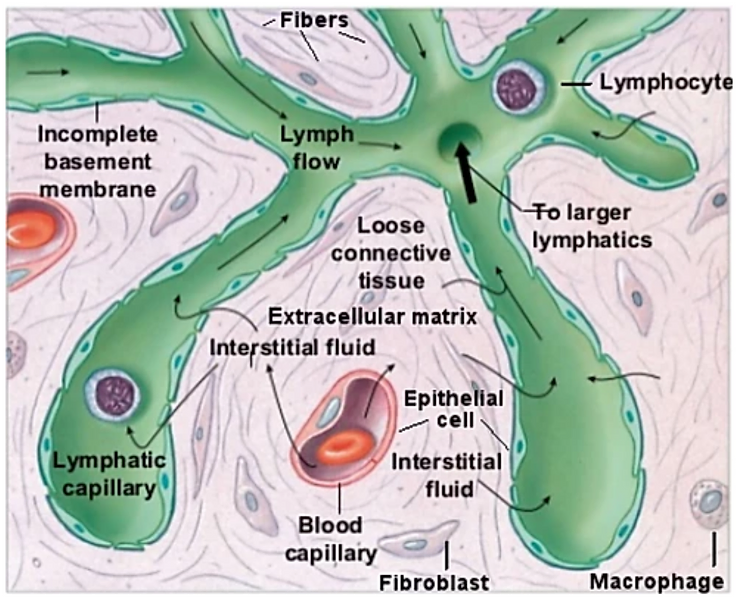

Decompensated acidosis of the body fluids causes erythrocytic or red blood cell membrane degeneration and genetic mutation causing the conditions of rouleau, membrane degeneration causing the spiking or knobing or ‘Corona Effect’, acanthocytosis, erythrocytic symplastism or red blood cell clotting, thrombosis and disseminated intravascular coagulation (DIC). There are at least eight major contributing toxic factors that cause the increased levels of acidity in the body fluids leading to a significant decline in the alkaline design of the major body fluids (See Illustration 2: Interstitial fluids of the Interstitium organ, the intravascular fluids and the Intracellular fluids) from their ideal pH of 7.365 to an unhealthy pH of 7.265 to 7.165.

Non-Invasive Diagnostic Intravascular and Interstitial Fluid Testing

In addition, we used our unique patent-pending non-invasive 3-D Bio-electro-scanning and non-invasive intravascular blood testing devices for testing and quantifying the biochemistry, including the pH of the intracellular fluids, the intravascular fluids and the interstitial fluids of the Interstitium, the largest organ of the human body. By measuring and comparing the biochemistry of all the body fluids it became clear that patients who tested positive for pathological blood coagulation or disseminated intravascular coagulation and positive SARS-CoV antibodies were all in decompensated acidosis of the interstitial fluids, including the interstitial fluids of the lungs leading to the genesis of oxygen deprivation, hypoxia and sudden death was not viral, bacterial or fungal.[33][34][35]